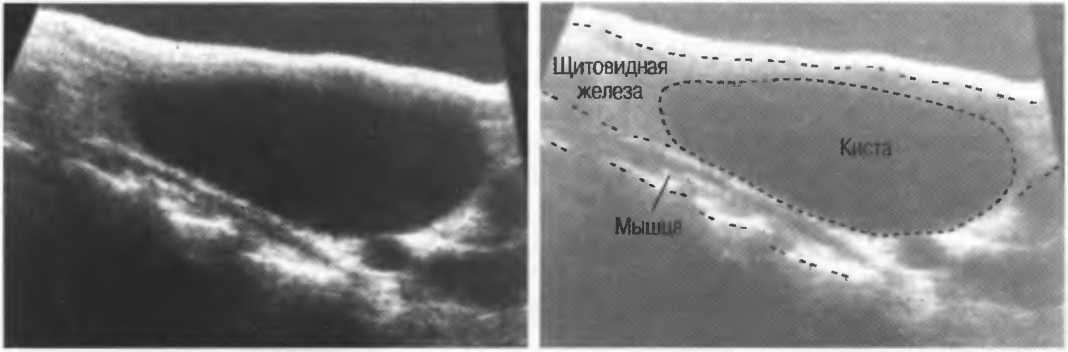

Кисты

Киста, как правило, визуализируется в виде анэхогенной зоны, при этом структуры, расположенные за кистой, обычно усилены: полость кисты анэхогенна, поскольку в ней нет структур с различным акустическим сопротивлением. В результате того что жидкость не поглощает ультразвук в такой же степени, что и ткань, эхо-сигналы от расположенных позади кисты структур гиперкомпенсированы сканером и выглядят усиленными — появляется эффект усиления задней стенки (рис. 14а,б).

Киста определяется в виде анэхогенной зоны с усилением по задней стенке. Если в кисте есть внутренние зхоструктуры, то они могут быть реальными или являться артефактами.

Рис. 14а. Заполненная жидкостью киста: полость кисты анзхогенна, имеется усиление задней стенки.